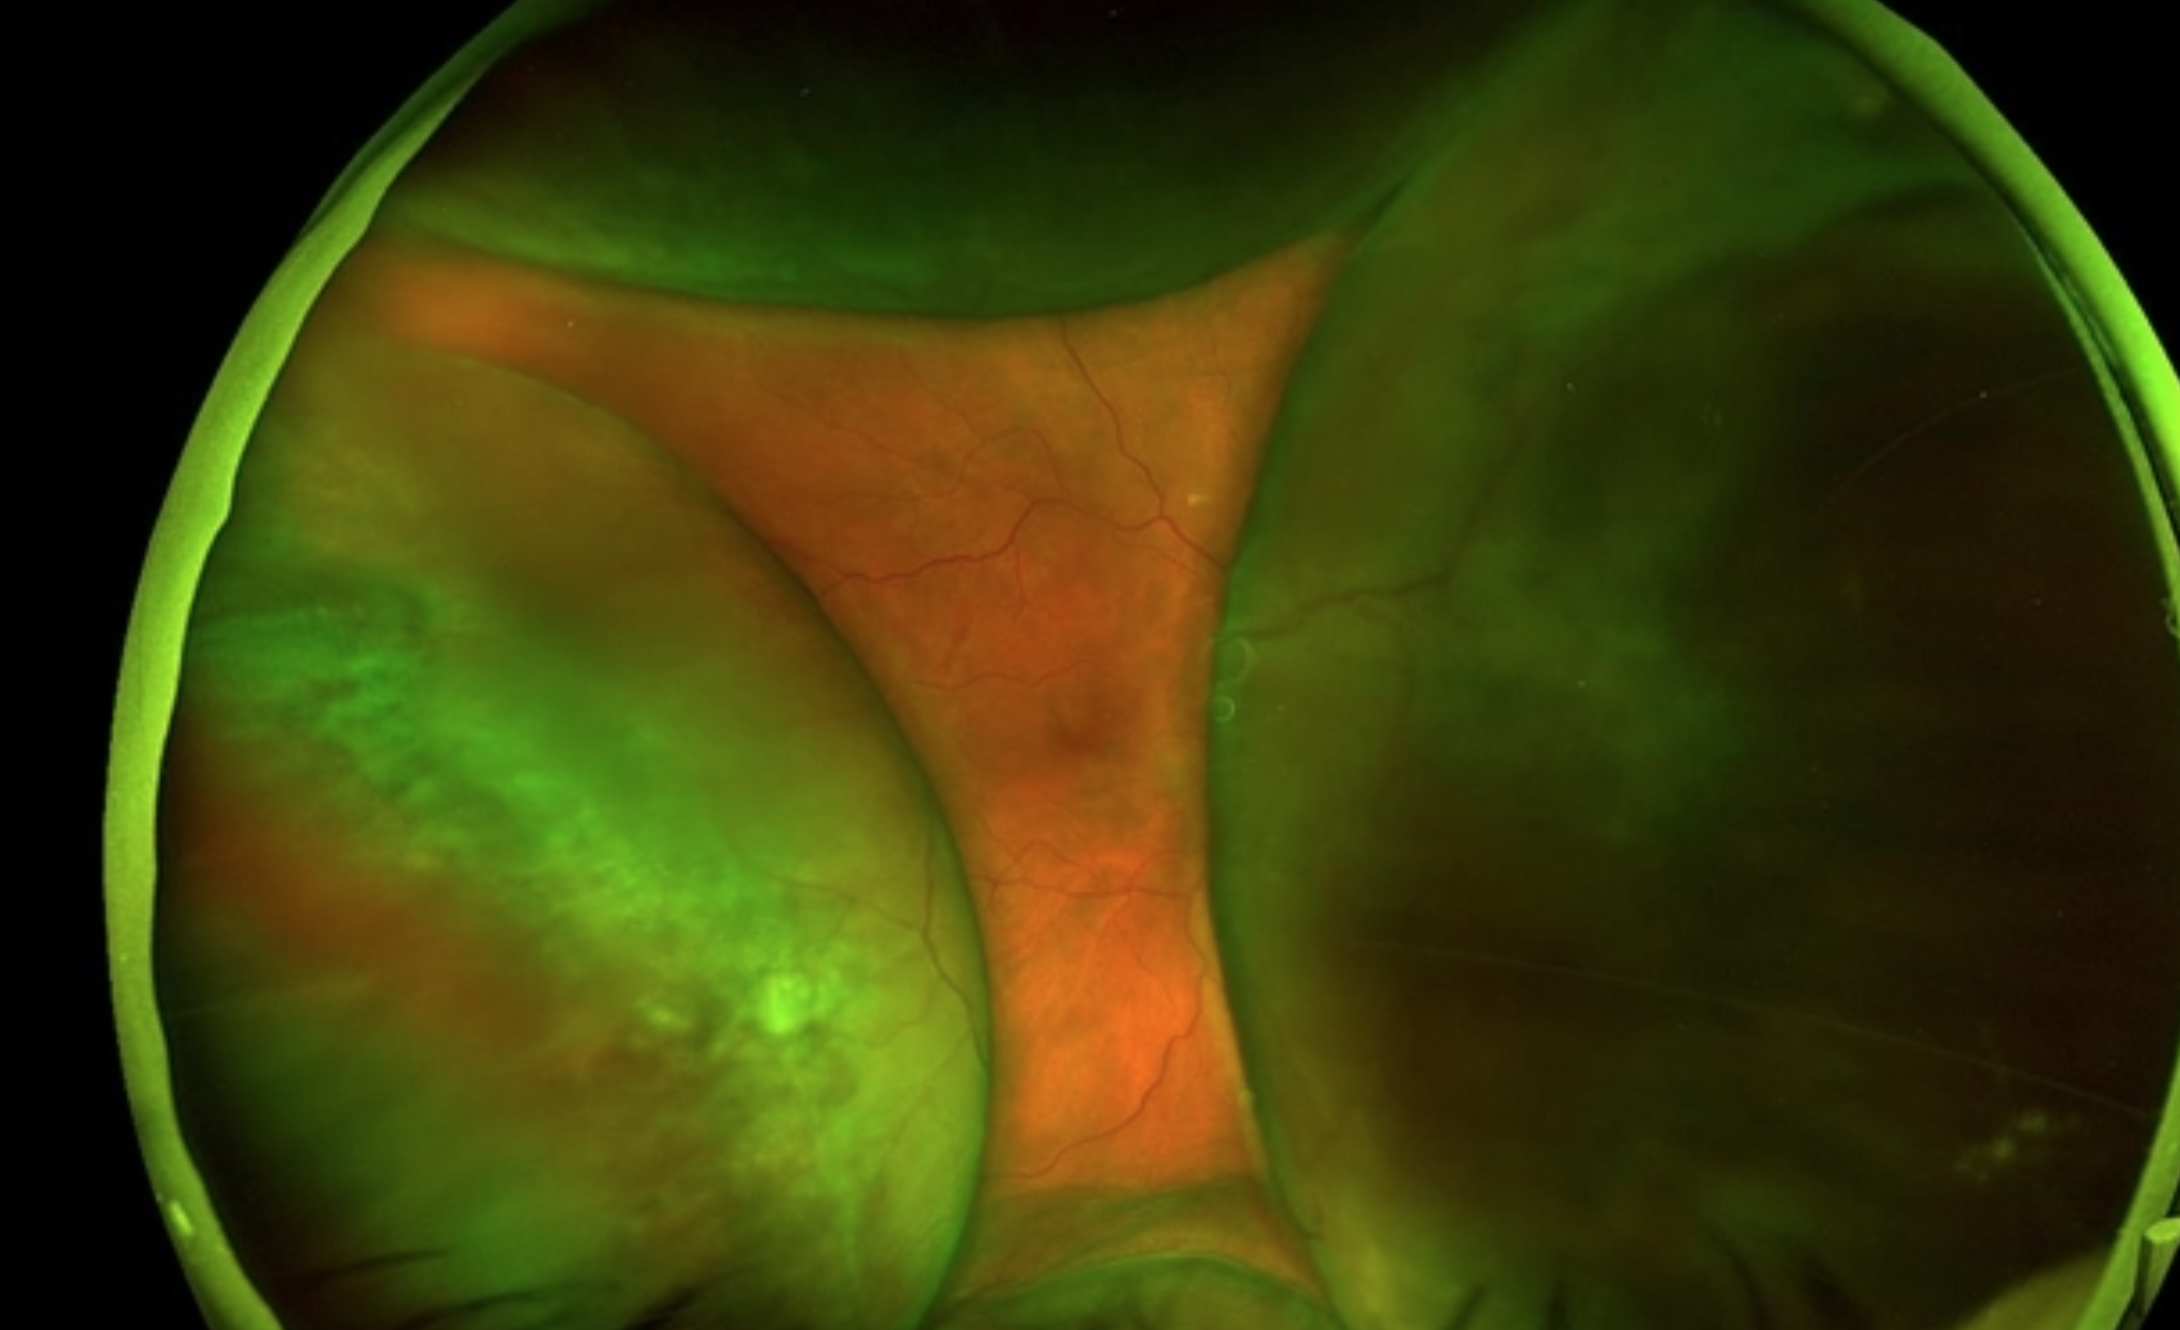

Severe enough = cause EXUDATIVE RETINAL DETACHMENT

Exudative RD (aka Serous RD) = type of retinal detachment where fluid collects underneath retina without hole or tear in the tissue

Leaking blood vessels or an inflamed choroid pumps fluid into subretinal space

Vascular (Coats' Disease)

Patient: Young boys (as we discussed with Leukocoria)

Logic: The "lightbulb" telangiectatic vessels leak massive amounts of lipid and serous fluid, lifting the retina

Exudative retinal detachments also possible